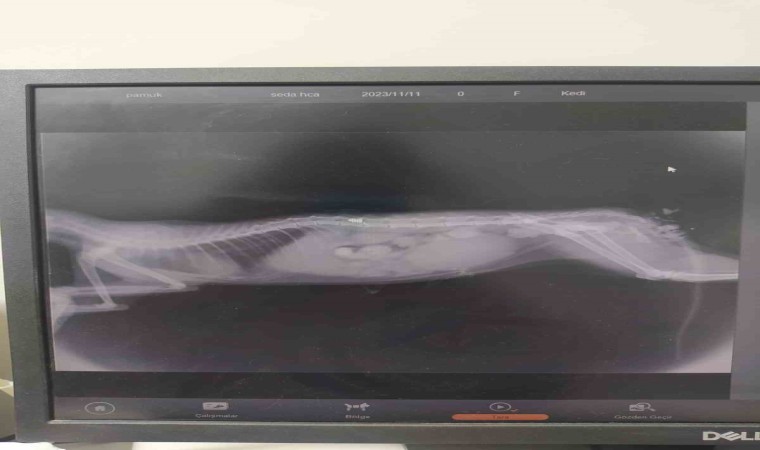

Osmaniye’de yerel hayvan koruma derneği üyesi Seda Ermiş, sokakta besleme yaptığı sırada arka ayakları tutmayan bir yavru sokak kedisi buldu. Kediye araba çarptığını düşünen Ermiş, hemen kediyi veterinere götürdü. Veterinerde çekilen röntgende kedinin kaza yapmadığı omuriliğinde havalı tüfek mermisi bulunduğunu ve durumunun kritik olduğunu gören Ermiş, zaman kaybetmeden yaralı kediyi alıp ameliyat için Adana’da özel bir veteriner kliniğine götürdü. Burada yapılan başarılı operasyonla omurilikte bulunan ve yürüme duyularına zarar veren saçma çıkarılarak kedinin fizik tedavisine başlandı.

Havalı tüfek mermisinin yürüme sinirlerine zarar verdiğini söyleyen veteriner hekim İsmail Serdar Sayar, "Osmaniye’den geldi belinden saçmayla vurulmuş ve L1 omurga dediğimiz omura saçma saplanmış. Ameliyatında şunu gördük o saçma kemiği kırıyor içeri giriyor spiral kont dediğimiz omurilik sinirinin üzerine yapışmış. Biz usulüne uygun bir şekilde çıkardık, ancak ciddi anlamda hasar vardı omuriliğinde gerekli işlem yapıldı. Şuanda genel durumu iyi ama yürüyüp yürümemesi biraz şansına kalmış. Çünkü siniri bizim onarma yenileme şansımız yok.Umarım iyi bir netice olur ama çok sevimli masum bir arkadaş." Diye konuştu.